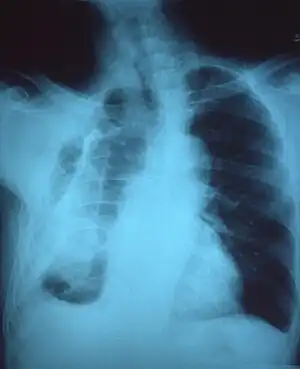

CXR of an individual affected by fibrothorax (consequence of tuberculosis)

Extensive left-sided fibrothorax

Chest radiograph displaying inhomogeneous opacification of the left half of the chest that is fibrothorax

A fibrothorax can typically be diagnosed by taking an appropriate medical history in combination with the use of appropriate imaging techniques such as a plain chest X-ray or CT scan.[3] These imaging techniques can detect fibrothorax and pleural thickening that surround the lungs.[7] The presence of a thickened peel with or without calcification are common features of fibrothorax when imaged.[3] CT scans can more readily differentiate whether pleural thickening is due to extra fat deposition or true pleural thickening than X-rays.[3]

If a fibrothorax is severe, the thickening may restrict the lung on the affected side causing a loss of lung volume.[7] Additionally, the mediastinum may be physically shifted toward the affected side.[3] A reduction in the size of one side of the chest (hemithorax) on an X-ray or CT scan of the chest suggests chronic scarring.[6] Signs of the underlying disease causing the fibrothorax are also occasionally seen on the X-ray.[6] A CT scan may show features similar to those seen on a plain X-ray.[7] Lung function testing typically demonstrates findings consistent with restrictive lung disease.[6]